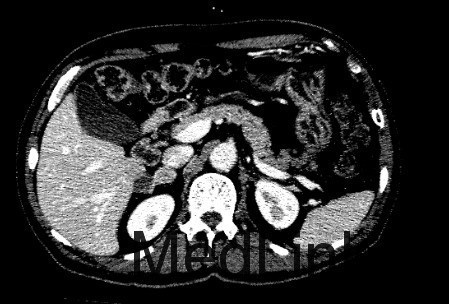

查体: 左上腹外侧见手术切除,余无异常。 辅助检查: 1、检验 白细胞WBC 6.15x10^9/L,血红蛋白Hb 165 g/L,血小板PLT 173x10^9/L;乙肝表面抗原HBsAg(-),乙肝核心抗体HBcAb(+);AFP, CEA、CA125、CA19-9均正常范围 2、影像学 CT:肝S6内缘包膜下结节(19×17mm、19×19mm,),考虑肝细胞癌可能性大,建议进一步检查;其相邻低密度结节,不除外肝囊肿。 2.右侧肾上腺结节,考虑转移瘤可能性大。 3.双肾囊肿。

临床诊断 肝细胞癌 治疗: 手术切除右侧肾上腺转移瘤和右肝肿瘤 术后病理: 1、(肝)送检4x3x2cm灰褐色组织一块,切面灰黄,质软。 镜下:送检肝组织内见境界较清楚的胶原纤维包裹的坏死结节,其内可见肿瘤残影,建议结合临床患者是否行介入等治疗,则可符合治疗后改变,未见残留肿瘤细胞。另一组织提示增生的肝细胞Glypican-3灶性(+),CD34显示增生的结节毛细血管化。 特殊染色:网状纤维染色显示肝细胞索增生。 结合HE形态及免疫组化结果,病变符合肝细胞癌。 2(肾上腺结节)送检5x3x3cm淡黄组织一块,可见直径2cm灰白结节。 镜下:肾上腺组织内见肝细胞癌浸润。